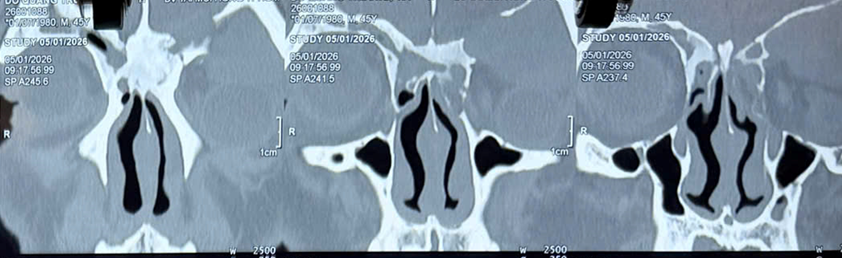

Hình ảnh CTScan: U nhầy xoang trán (T) lan hốc mắt (T)

Khi được chụp phim kiểm tra chuyên sâu, các bác sĩ phát hiện một khối u nằm trong xoang trán (vùng trên hốc mắt). Khối u này phát triển chậm trong thời gian dài, làm mòn và vỡ xương, từ đó chèn ép nhãn cầu, khiến mắt bị đẩy ra ngoài.